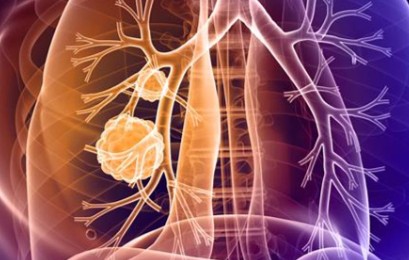

- 청색증

- 설명: 폐 기능이 심하게 저하되면 몸에 산소가 부족해져 입술이나 손톱이 파랗게 변하는 청색증이 나타날 수 있습니다. 이는 즉시 응급 처치가 필요한 매우 위험한 상태입니다.

- 의식 혼미

- 설명: 드물지만, 폐렴이 심하게 진행되면 의식이 혼미해지거나 정신을 잃는 경우가 발생할 수 있습니다. 이는 특히 노인에게서 나타나기 쉬운 증상입니다.